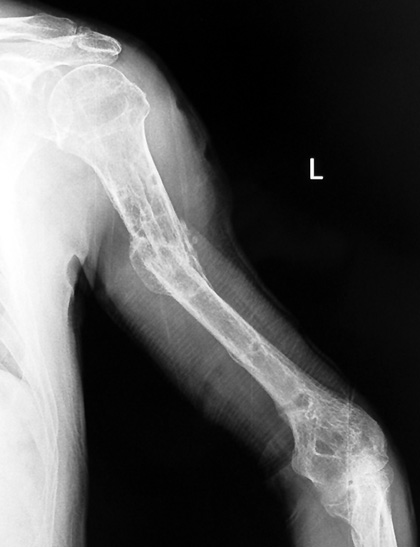

Humerus Psödartroz

Konservatif veya konvansiyonel cerrahi yöntemlerle tedaviye rağmen en az 4 ay geçmesine karşın kaynama sağlanamaması durumunda kırığı artık psödartroz olarak kabul etmek gerekir. Rosen ise 3-4 ay gibi bir sürede kaynama sağlanamamasını kaynama gecikmesi, 6-8 ay gibi bir sürede kaynama sağlanamamasını ise psödartroz olarak değerlendirmiştir. Humerus psödartrozlarının tedavisinde değişik plak-vida uygulamaları, intramedüller fiksasyon cihazları ve tek başına ya da kombine greftleme yöntemleri gibi cerrahi yöntemler ve elektrik stimülasyonu gibi konservatif yöntemler kullanılmasına rağmen, her zaman istenilen sonuçlar elde edilememiştir.

Humerus psödartrozlarının tedavisi için bir çok yöntem tanımlanmış olmasına rağmen, çoğu olguda tekrarlayan ameliyatlar gerekmekte, ameliyat sayısının artması ile orantılı olarak başarı oranı düşmektedir. Bu yüzden humerus psödartrozlarının tedavisi kadar, bu güç komplikasyonun azaltılmasına yönelik önlemler alınması da önemlidir. Humerus 1/3 distal-orta bileşim yerindeki kırıklar, transvers veya kısa-oblik kırıklar, segmenter kırıklar, açık kırıklar, patolojik kırıklar, sistemik hastalığı olan hastalar, obez hastalar, kronik omuz-dirsek eklem hareketleri kısıtlı olan, alkol ve sigara alışkanlığı olan, osteoporotik hastalar psödartroza eğilimli hastalardır. Seçilen tedavi yönteminin uygulanışı ile ilgili teknik hatalar ve yetersiz takiplerde humerus kırıklarında psödartroz oranlarını artırmaktadır.

Humerus psödartrozlarının nedenleri mekanik ve biyolojik yönden bakıldığında diğer kırıklarda görülen psödartroz nedenleri ile benzerdir. Kırık bölgesinde engellenememiş hareket, kırık fragmanlar arasında ortadan kaldırılamamış mesafe, kanlanmanın bozulması gibi faktörler kaynamanın gerçekleşmemesine yol açar. Kaynama ancak psödartroz nedenleri ortadan kaldırılabildiğinde sağlanabilir. Kırık bölgesindeki hareketin önlenmesi rijit fiksasyonla sağlanabilir. Genellikle psödartroz bölgesinde kemik kalitesi daha önceki tedaviler nedeni ile iyi olmayacağından plak-vida veya intramedüller implantlarla stabil fiksasyon sağlamak zordur. Trotter ve Dobozi bu endişeden dolayı plak-vida fiksasyonunu medulla içine uyguladıkları kemik çimentosu ile güçlendirmeye çalışmışlardır. Yöntemin medülller kanlanmayı bozabilme, kemik çimentosunun psödartroz hattına sızarak kaynamayı olumsuz etkileme gibi dezavantajları vardır. İntramedüller implantlarda rotasyonel stabiliteyi ve humerus yük binen bir kemik olmadığı için psödartroz bölgesindeki mesafenin kapatılmasını sağlamak her zaman mümkün olmamaktadır. Taze kırıkların intramedüller implantlarla tedavisi sırasında bile kırık bölgesinde distraksiyon gelişebilir. Humerus psödartrozlarının intramedüller implantlarla tedavisinde uygulama tekniğine bağlı olarak subakromial sıkışma sendromu ya da dirsek problemleri ile karşılaştırılabilmektedir.